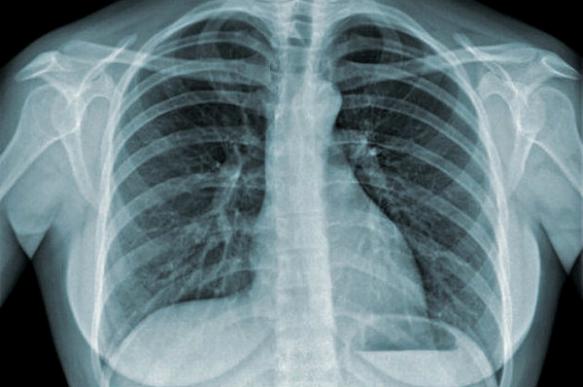

Новые данные о фиброзе легких приближают лечение болезни

Ученые из Медицинского центра Университета Вандербильта (VUMC) и Научно-исследовательского института трансляционной геномики (TGen) в Фениксе, США, обнаружили новые генетические и клеточные изменения, которые происходят у людей с фиброзом легких (ФЛ).

Их результаты, опубликованные в журнале Science Advances, должны помочь в поиске новых способов лечения или профилактики заболевания, вызывающего рубцевание легких.

Исследователи использовали передовые микрофлюидные методы и секвенирование одноклеточной РНК для выявления изменений в профиле экспрессии генов в более чем 100 тыс. отдельных клеток легкого от 20 пациентов с ФЛ. Они идентифицировали множество ранее не описанных типов клеток, которые экспрессировали высокие уровни коллагена и других компонентов внеклеточного матрикса, накапливающихся при ФЛ.